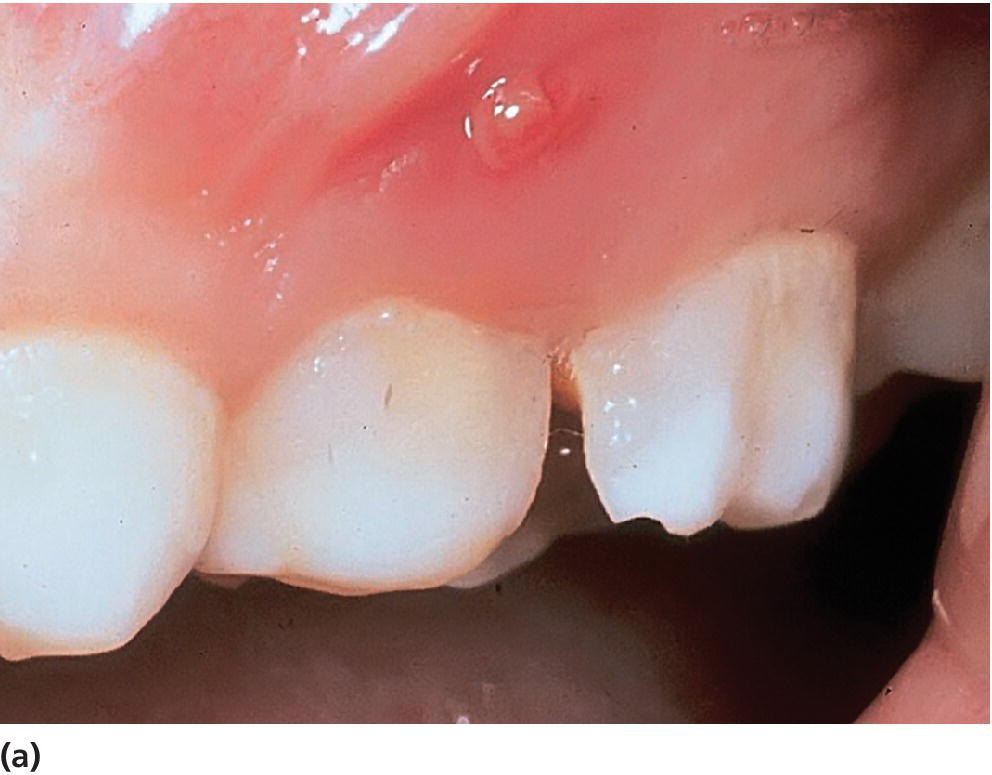

From pocketdentistry.com

7 Case History and Clinical Examination Pocket Dentistry Abscess Tooth Or Sinus Infection In cases where a dental abscess forms in the upper teeth, the infection can extend into the surrounding bone and tissues, reaching. A tooth abscess is a localized infection caused by bacteria within a tooth or gum, while a sinus infection occurs when the sinus cavities become inflamed and infected due to. Without proper treatment, tooth infections can spread to. Abscess Tooth Or Sinus Infection.

From dentaldisaster.com

periodontal abscess Abscess Tooth Or Sinus Infection In addition to examining your tooth and the area around it, your dentist may: If that happens, the infection might spread to your sinuses, open spaces in your. In fact, pain in the upper back teeth is a fairly common symptom with sinus. Without proper treatment, tooth infections can spread to other areas of. A tooth infection or “tooth abscess”. Abscess Tooth Or Sinus Infection.

From periobasics.com

Periodontal abscess and its treatment Abscess Tooth Or Sinus Infection If the abscessed tooth is near your sinus, it can create a hole between your tooth and your sinus. A tooth infection or “tooth abscess” is a collection of pus and bacteria that forms inside the tooth or gum. Without proper treatment, tooth infections can spread to other areas of. In fact, pain in the upper back teeth is a. Abscess Tooth Or Sinus Infection.